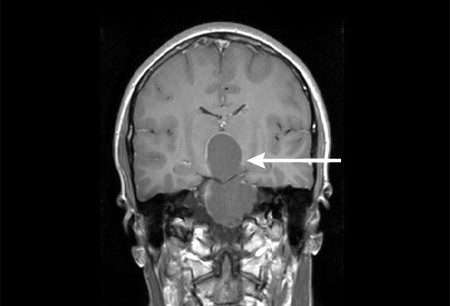

მეტი - თავის ტვინის მაგნიტურ რეზონანსული გამოსახვა (MRI):

შესაძლოა იყოს ნორმალური ან გამოავლინოს ჰიპოფიზის პათოლოგია, როგორიცაა ექტოპიური ჰიპოფიზის უკანა წილის ან ცნს-ის ავთვისებიანი მდგომარეობები

- თავის ტვინის მაგნიტურ რეზონანსული გამოსახვა (MRI):

შერეული სოლიდური/ცისტური სიმსივნე კალფიციკაციებით